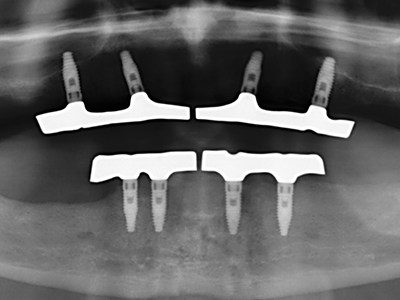

Когато се извършват хирургични процедури върху кост в непосредствена близост до чувствителни структури като кръвоносни съдове или нерви, ротиращите инструменти създават значителен риск за ятрогенно нараняване. Пиезоелектрическите апарати могат да бъдат от помощ при препарация на костно покритие и отстраняване на твърда кост близо до нерви, особено за оголване на нервите след ятрогенно нараняване, както и по време на латерализация на нервите за резекционни и реконструктивни процедури или поставяне на имплант (Фиг. 17-20). Лекият контакт между пиезонакрайника и нерва по принцип не води до нараняване, но ако действате непредпазливо с трионообразни движения или приставки за остатъчен костен субстрат, може да причините временно или перманентно увреждане на нерва. Въпреки това, рискът от увреждане се счита за много по-малък, отколкото при употреба на триони или ротиращи инструменти (Pereira, Gealh et al. 2014).